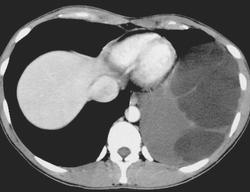

Медиастинальная тератома

ID: 18216 Mediastinal teratoma Dr Roberto Schubert - 19 Jun 2012